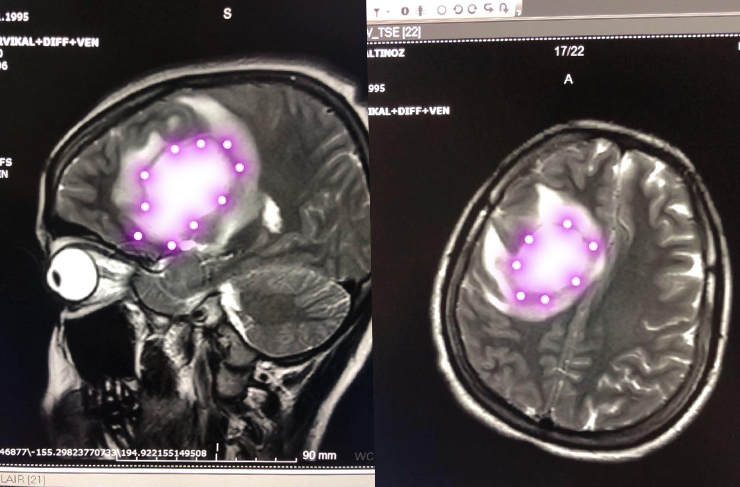

“5x5x4.5 Santimlik Tümörü Çıkardık”

Ameliyat sonrası bebeğin ve anne adayının sağlık durumunun iyi olduğunu ifade eden Op. Dr. Özkan Çeliker, nöronavigasyon yöntemle gerçekleştirdikleri ameliyat hakkında bilgiler vererek; “Bize başvuran hastamıza uyguladığımız tetkikler sonucu, beyninde tümör tespit ettik. Ardından beş aylık hamile hastamızı onkoloji konseyinde değerlendirmeye aldık. Gerçekleştirilen değerlendirme sonucunda, hastamızın bebeğini de koruyacak şekilde ameliyatına karar verdik. Nöronavigasyon cihazıyla hedefe yönelik küçük kesi açılarak, tümör dokumuzu subtotal olarak çıkardık.

Bu yöntem sayesinde, beynin derin bölgesinde bulunan tümörleri, çevre dokulara zarar vermeden çıkarmak mümkün olabiliyor. Patoloji sonucuna göre, hastamızın gebeliğinin 32. haftasında radyoterapi ve kemoterapi almasını sağlayacağız. Şuan hastamızın gebelik dönemi sağlıklı bir şekilde devam ediyor” dedi.